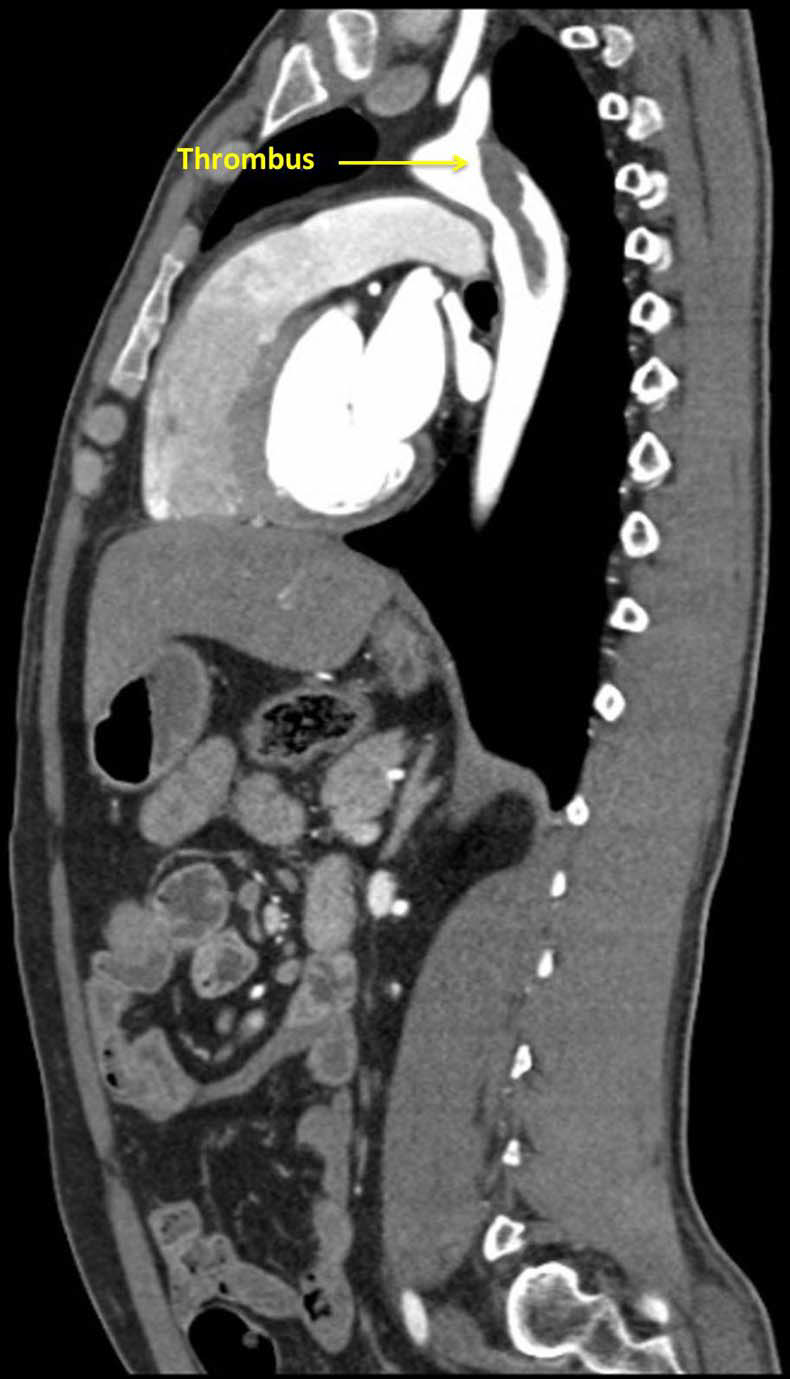

CT aortogram revealed a large, immobile thrombus fixed in the arch of aorta causing subtotal occlusion of the ostium of the left subclavian artery, with the rest of the aorta having no evidence of atherosclerosis or aortitis and the coronaries were normal (figures 1–3).

Figure 1 Coronal view of a large thrombus attached to the descending aorta at the origin of the subclavian artery.

Figure 3 Sagittal view of a large thrombus attached to the descending aorta at the origin of the subclavian artery.